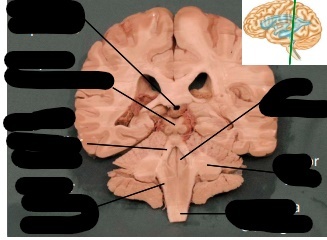

label, note important features